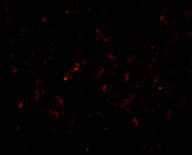

Immunofluorescence of GSTP1 in Human Lung cells with GSTP1 antibody at 20 μg/mL. |